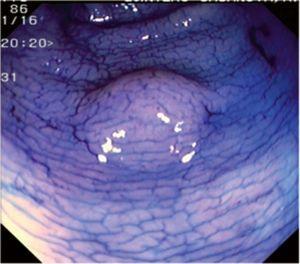

Fig. 3. Examples of flat lesions with conventional examination and after the application of indigo carmine 0.2-0.5%. a, b) Small flat adenoma, 3 mm in size. c, d) Large flat adenoma, 15 mm in size. e, f) Completely flat lesion (IIb in the Japanese classification). g, h) Depressed lesion, 3 mm in size) (IIc in the Japanese classification). I, J) Depressed lesion, 7 mm in size, histopathological study revealed submucosally invasive cancer (traditionally IIc in the Japanese classification, although recently such depressed lesions with a distinct central protrusion indicating submucosal invasion are termed IIc + Is). k, l) Flat elevated lesion with central depression, 10 mm in size, corresponding to a submucosally invasive cancer (IIa + IIc in the Japanese classification).